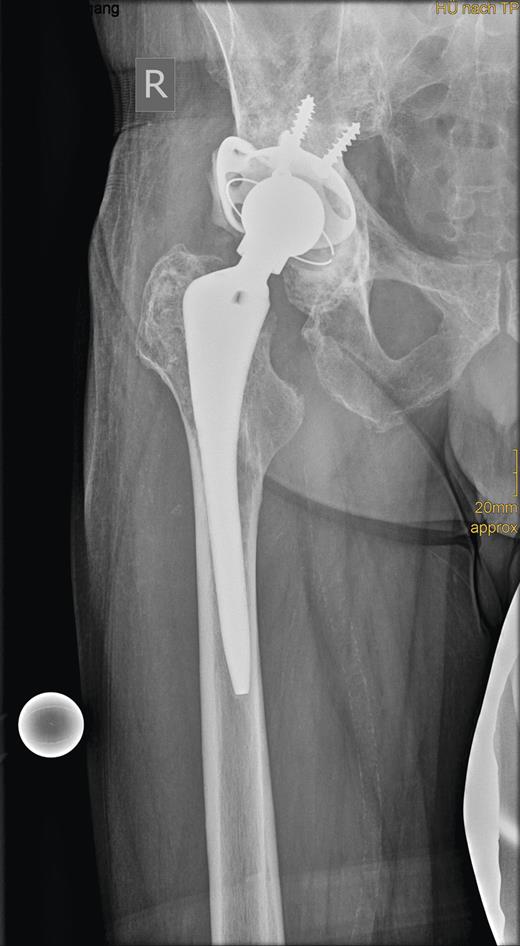

Radiograph showing the roof reinforcement ring with the cemented low profile cup after revision surgery.